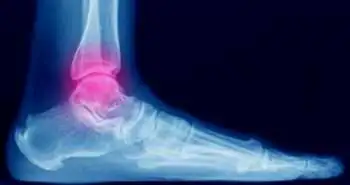

Effects of orthotic treatment for posterior tibial tendon dysfunction: A systematic review

This study was done to find if the orthotic treatment is efficient in treating flat foot.

A recent study demonstrated that the orthotic treatment for posterior tibial tendon dysfunction stages I and II (flat foot) is effective in relieving the pain. Orthotic treatment can be used for decreasing pain in patients with flat foot. However, more research is required for high-intensity monitored exercise programmes and individualized orthotic treatment.

It was concluded that the orthotic treatment helped in lowering the pain in the early stages of flat foot.